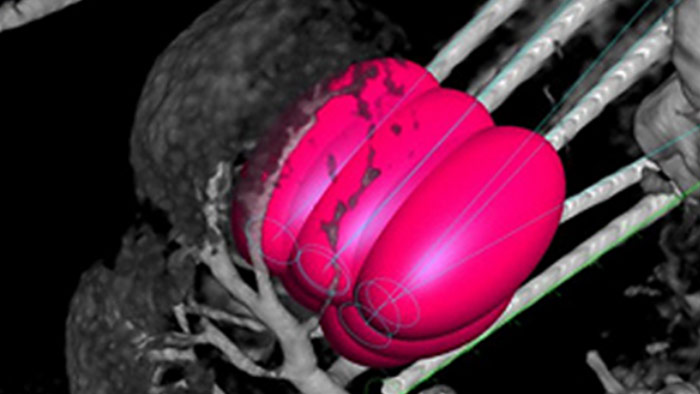

SmartCT bietet Ihrem Labor dank der einfachen Steuerung von erweiterten Funktionen für 3D-Erfassung, Darstellung und Messung am Tisch zusätzliche Flexibilität und Effizienz. Die halbautomatischen und über den Touchscreen steuerbaren Segmentierungsaufgaben beschleunigen die 3D-Bildanalyse. Um klinische Anwender bei der 3D-Bildgebung zu unterstützen, bietet SmartCT schrittweise Anleitungen für die gesamte 3D-Bildgebung. So können Sie das System problemlos bedienen und Ihren Patienten eine hervorragende Versorgung bieten.

Die perkutane Ablation (Hochfrequenz-, Mikrowellen- und Kryoablation) ist eine etablierte, minimal-invasive Behandlungsmethode für Nieren-, Leber-, Lungen- und Knochentumore. Dabei ist es besonders wichtig, den Tumor abzugrenzen und eine geeignete Anzahl an Nadeln und notwendigen Nadelverläufen festzulegen, damit der gesamte Tumor behandelt werden kann, ohne das umliegende Gewebe zu schädigen. Durch die präzise Navigation zur relevanten Läsion bei niedriger Strahlendosis und ohne Neupositionierung der Nadel werden die Erfolgschancen erhöht und das Komplikationsrisiko bei Biopsien und Ablationen reduziert. Der Endpunkt der Ablationsbehandlung kann mittels 3D-Bildgebung verifiziert werden, während sich der Patient noch auf dem Tisch befindet.